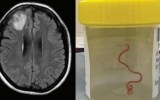

The live Ophidascaris robertsi roundworm was extracted – still ‘wriggling’ – from the brain of the anonymous 64-year-old New South Wales woman at Canberra hospital.

It marks the first case of the parasite, typically found in carpet pythons, being found in a human.

In 2022, the patient began experiencing forgetfulness and worsening depression, and underwent an open brain biopsy in June that year – leading to the discovery of the live roundworm.